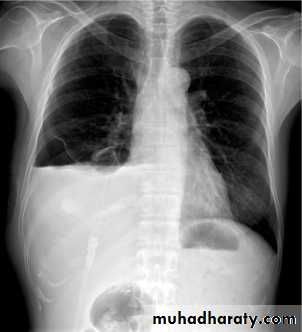

CXR of adult male PA and lateral views, it shows :Normal both lung fields ,Central cardiac shadow, Central trachea, central mediastinum, No boney lesions, no soft tissue abnormalitiesnormal radiologic anatomy of the chest Look carefully on both diaphragmatic cruse costo & cardio phrenic angles. Useful in detection of pleural effusion